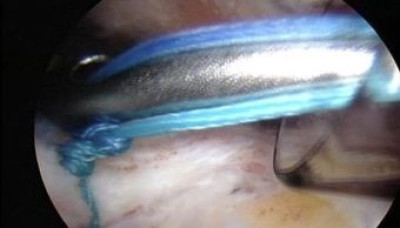

Se han pasado los hilos a través del tendón del supraespinoso